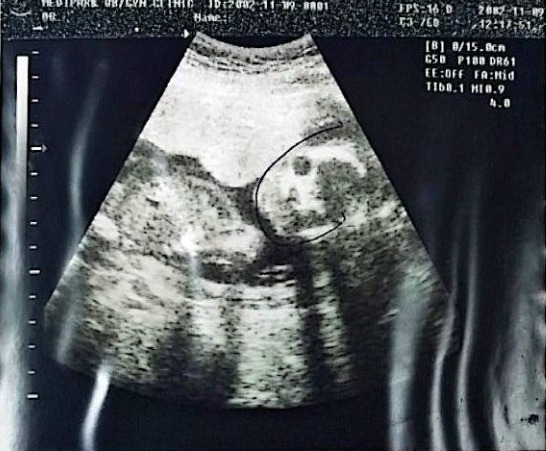

KakaoTalk_20250912_104546807.jpg 2002.11.9